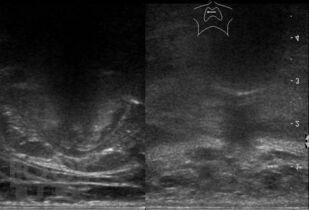

В основу монографии положены материалы собственных исследований и практический опыт использования ультразвуковых методов диагностики при обследовании пациентов после хирургических вмешательств на щитовидной железе. Продемонстрированы диагностические возможности ультразвукового исследования в оценке состояния оперированной щитовидной железы в раннем и отдаленном послеоперационном периоде. Обобщена, систематизирована и представлена ультразвуковая семиотика зоны операции в ближайшие сроки после хирургических вмешательств и отражена динамика выявленных изменений. Убедительно показано, что ультразвуковое исследование может быть эффективным методом послеоперационного наблюдения.